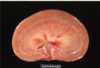

hydronephrosis

hydronephrosis/hydroureter

What occurred to this kidney?

chronic hydronephrosis

pressure atrophy